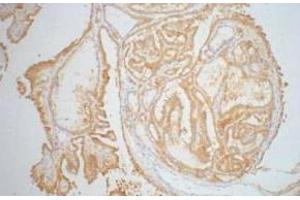

Découvrez des anticorps Galectin 3 fiables issus d’une large sélection de fabricants renommés. Notre portefeuille permet une détection précise de Galectin 3 dans plusieurs espèces, y compris Human, Mouse, Rat, Rabbit, Dog, Pig, Rhesus Monkey, Bat, Cow, Guinea Pig, Horse, Monkey, et prend en charge diverses applications de recherche telles que WB, IHC, FACS, ELISA, IF.

LGALS3 Reactivité: Humain WB, IHC, IF Hôte: Lapin Polyclonal unconjugated